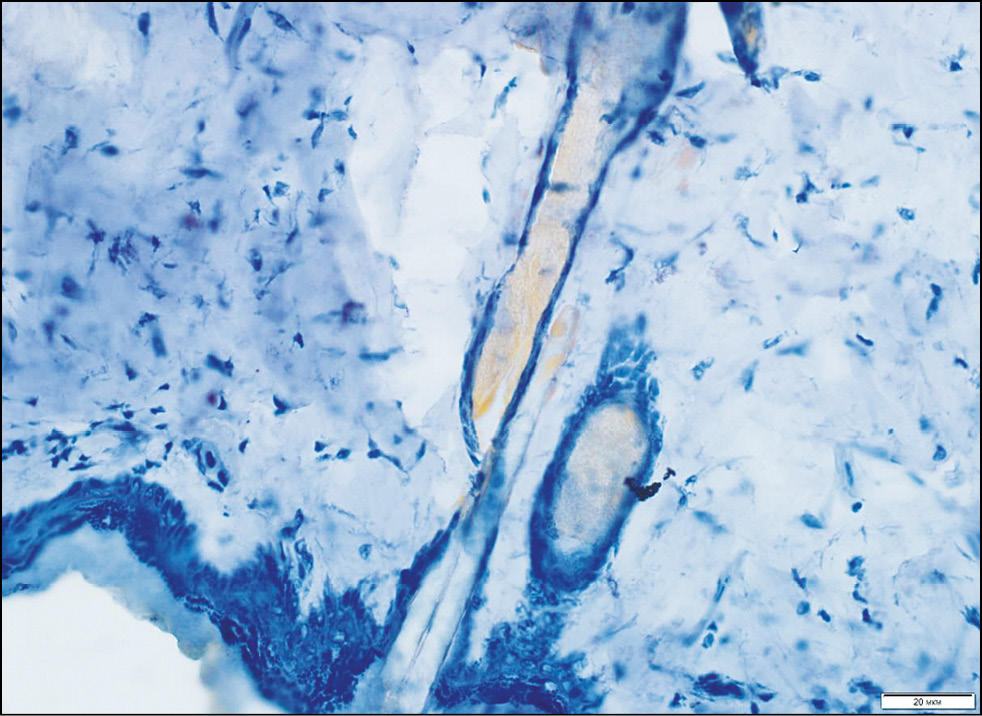

Рис. 4. Гистологическая картина кожи спины крысы через 15 мин после нанесения топического средства с 0,4% Сферометаллохлорином™. Окраска Суданом III, х200.

Fig. 4. Histological picture of the skin of the back 15 minutes after application of a topical agent with 0.4% Spherometallochlorin™. Painting by Sudan III, x200.

Рис. 5. Гистологическая картина кожи спины крысы через 30 мин после нанесения топического средства с 0,4% Сферометаллохлорином™. Окраска Суданом III, x100.

Fig. 5. Histological picture of the skin of the back 30 minutes after application of a topical agent with 0.4% Spherometallochlorin™. Painted by Sudan III, x100.

Подэтап 1Б. При исследовании гистологической картины до нанесения геля (рис. 3) со Сферометаллохлорином™ эпидермис и дерма интактны. Через 15 мин экспозиции (рис. 4) заметно скопление суданположительного материала в придатках кожи; кроме того, наблюдается его распространение рядом с волосяными фолликулами в интерстиций дермы. Через 30 мин экспозиции (рис. 5) отмечается распространение суданположительного материала в интерстиции в виде мелких капель по ходу коллагеновых волокон на глубину до подкожно-жировой клетчатки. Через 45 мин экспозиции в препарате визуализируются крупные сформированные липидные капли в дерме и более интенсивно прокрашенные липидные капли в подкожно-жировой клетчатке.

На основе полученных данных можно сделать вывод, что оптимальным временем экспозиции геля с фотосенсибилизатором является 30 мин, поскольку на этом этапе гель проникает в дерму по ходу коллагеновых волокон на глубину до подкожно-жировой клетчатки, что является обязательным условием для проведения процедуры ФДТ.

По данным гистологического исследования с окраской Суданом III, проникновение топического средства с 0,4% Сферометаллохлорином™ на 15-й мин недостаточно, на 30-й мин является оптимальным, а на 45-й мин препарат собирается в более крупные капли. В результате проведения курса процедур в режиме 1 раз в 7 дней, № 5 происходит активация макрофагов, которые выделяют матриксные металлопротеазы, расщепляющие избирательно коллаген III типа, который впоследствии трансформируется в коллаген I типа. Кроме того, по данным иммуногистохимического исследования экспрессии маркера пролиферации клеток Ki-67, процедура ФДТ является безопасной.